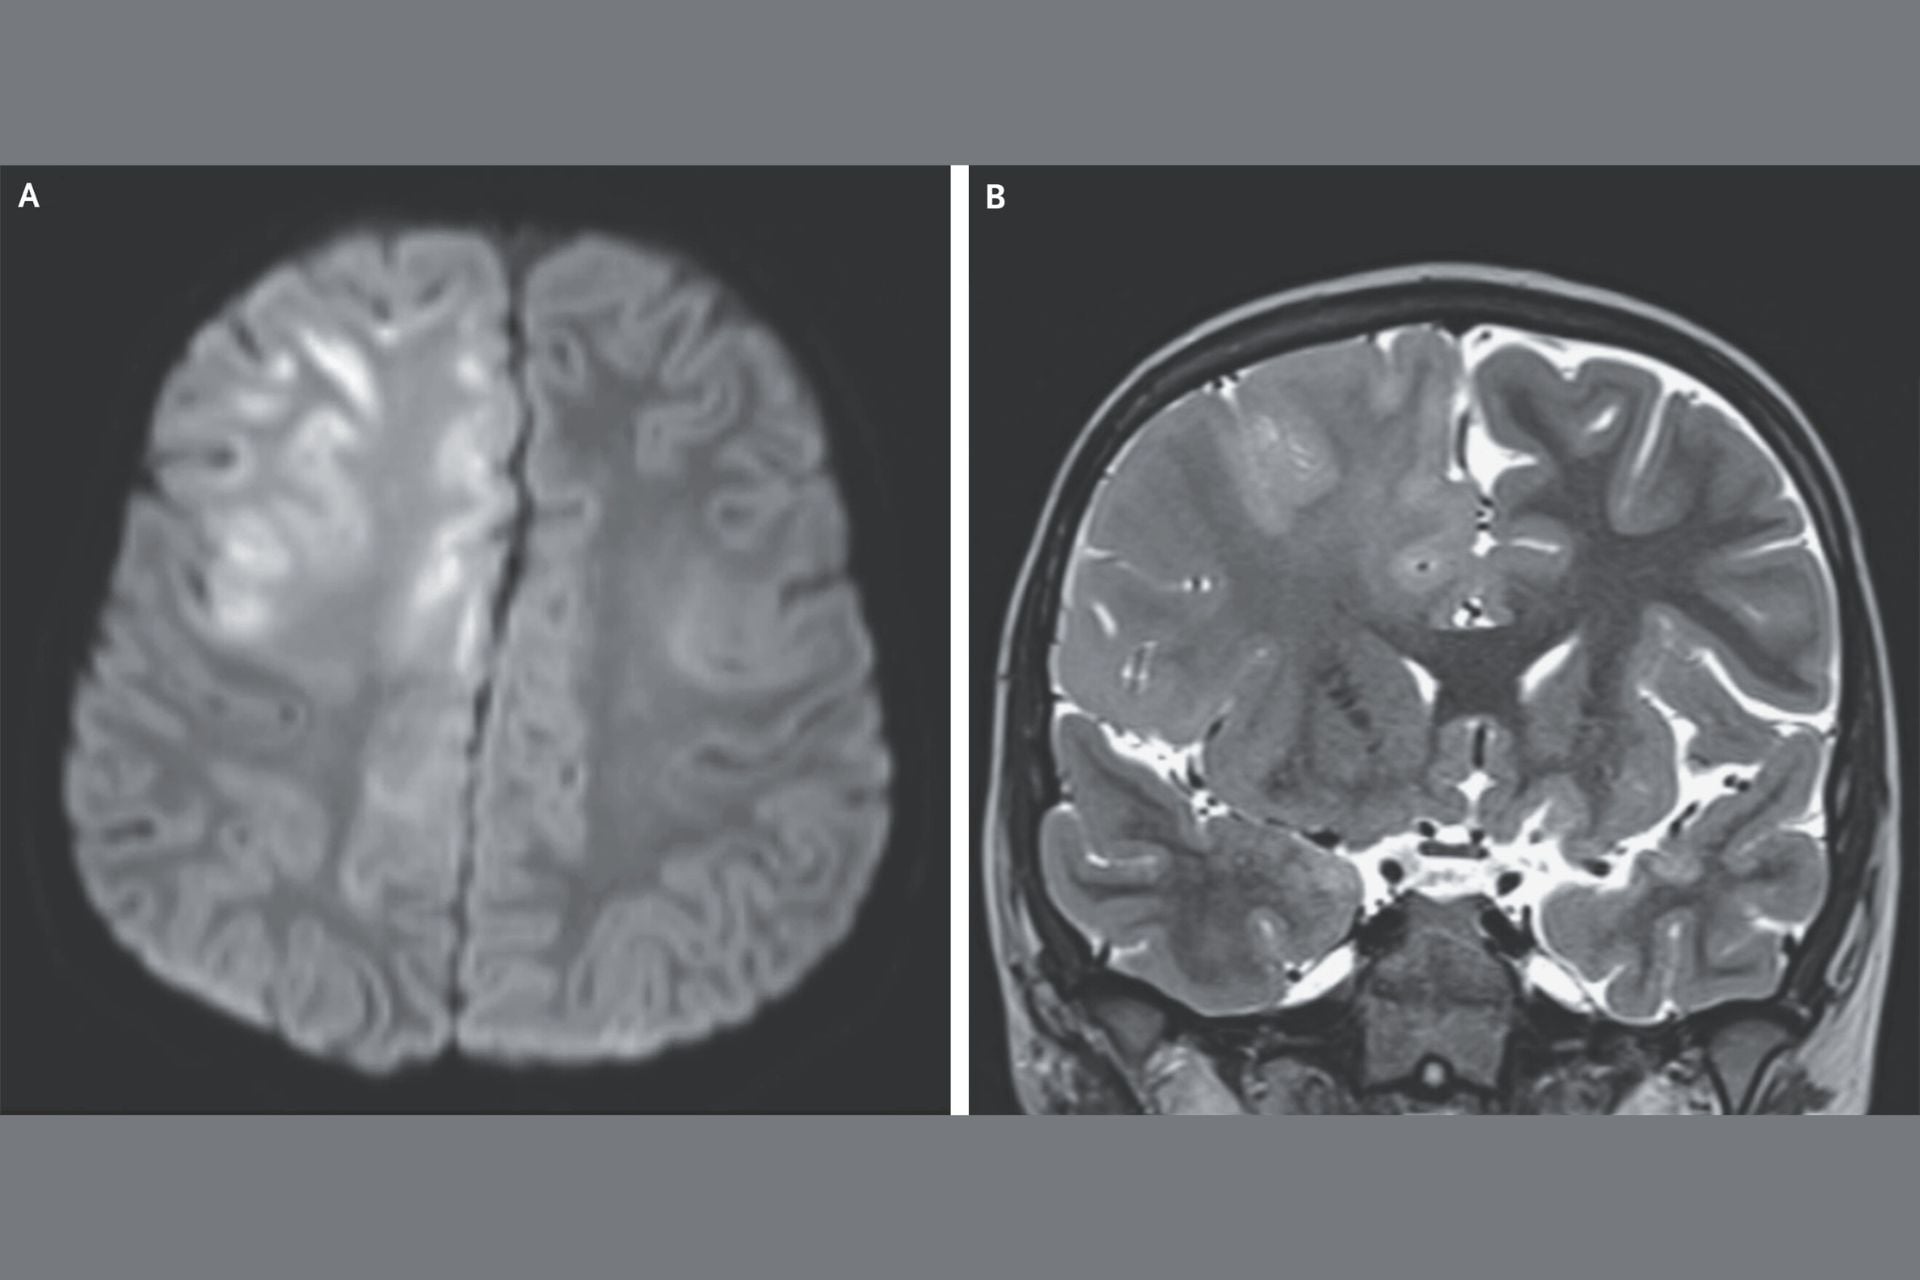

In this instance, the 7-year-old boy visited the doctors three months into having seizures and cognitive decline. He was no longer able to speak, and an MRI scan (seen in the top image) revealed extensive damage to the brain. Though the boy’s MRI results didn’t quite match the typical case of SSPE, the boy had contracted measles at 7 months of age while living in Afghanistan, a country where the virus is endemic. Tests of his spinal fluid also revealed levels of antibodies to the measles virus. That, coupled with his infection history and EEG results, led doctors to diagnose him with SSPE.

“The atypical imaging in our case highlights the diversity of MRI features of SSPE, but also clinicians need to be aware of the signs and symptoms of SSPE in previously unvaccinated individuals who have contracted measles,” report author John Crawford, the division chief of pediatric neurology at the University of California, Irvine’s School of Medicine, told Gizmodo.